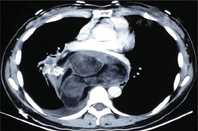

女性,45岁,因"体检发现后纵隔占位6 d"于2015年4月13日入院。查体无明显异常。实验室及器械检查显示:胸部CT显示右后纵隔内可见一较大不规则形异常密度影,最大横断面范围约160 mm×103 mm,内部密度混杂多样,可见多发脂肪成分及钙化灶,见多发分隔及多囊性病灶。增强后病变部分可见强化,部分未见强化,纵隔内心脏、血管、支气管及食管可见明显受压推移改变;纵隔、肺门未见肿大淋巴结影,右侧胸腔可见积液,胸膜未见增厚,考虑畸胎瘤(图1)。心电图示窦性心律,正常心电图。上消化道造影示食管中下段被纵隔右后方块状物推移至左侧;食管黏膜光整,形态规则,蠕动正常(图2)。肺功能检查显示:用力肺活量(forced vital capacity,FVC)为2.21 L,占预计值的77.2%;第1秒用力肺活量(forced vital capacity in the first second,FEV1)为1.79 L,占预计值的74.8%;最大通气量(maximum ventilatory volume,MVV)为86.52 L/min,占预计值的103.2%;FEV1/ FVC%为80.8%,提示肺功能轻度损害,混合性肺通气功能障碍。心脏彩超显示:心脏结构及功能未见明显异常。血常规、肝肾功能、凝血功能、血液传播疾病检查示基本正常。2015年4月20日,患者在双腔气管插管下行静脉复合麻醉,采用右胸后外切口从第6肋上缘进胸,术中见心脏后方巨大囊实性纵隔肿瘤,约18 cm×17 cm×10 cm,占据右后半胸腔。右下肺受压,部分粘连。肿瘤与主动脉、左下肺、右下肺、左右主支气管、食管、膈神经关系紧密,与两侧下肺均有粘连。手术切除完整的具有包膜多结节状肿物(图3)。切面灰白实性,呈鱼肉状,质地中等,界限清。病理诊断:高分化型脂肪肉瘤(图4)。患者病情恢复良好,术后第14天出院。

胸部CT扫描是诊断纵隔脂肪肉瘤主要的影像诊断方法,CT图像表现为囊性或囊实性肿块,内有多种不同密度的组织成分相互混杂分布,包括脂肪组织、水样成分、软组织成分等,骨化和钙化较常见。其CT值常为-100~80 HU,骨化部分CT值远高于此范围。但CT值大小不能完全鉴别分化良好的脂肪肉瘤和脂肪瘤。CT值越低,分化程度可能越高[7]。磁共振成像(magnetic resonance imaging,MRI)提示为混杂密度,不均匀的脂肪密度;可见不规则的线形及条索状高密度影,亦是重要的诊断方法。细针穿刺法组织学检查能诊断脂肪肉瘤,明确判断肿瘤良恶性[8],但很难鉴别病理分型。鉴别诊断主要是好发于前中纵隔的纵隔畸胎瘤,含三胚层组织成分。肿瘤内部密度不均,囊性、脂肪性、类实质性密度混杂存在,有时包含钙化甚至骨化组织,脂—液平面和水密度子囊为其特异性表现。脂肪肉瘤术前极易误诊为畸胎瘤,本例术前CT提示考虑畸胎瘤。